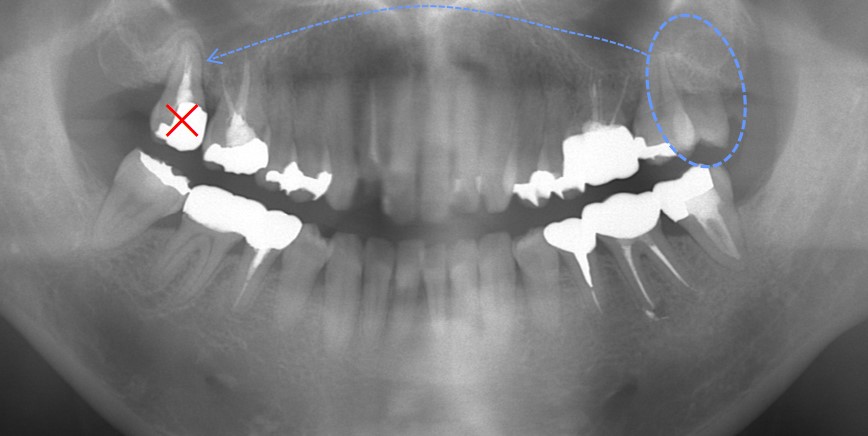

赤矢印の歯は歯根破折(根が割れている)しているため抜歯するしかありません。青矢印部分に細菌感染による大きな骨吸収が確認できます。

そこで、赤矢印の歯を抜歯して、黄色〇の親知らずを移植する計画としました。